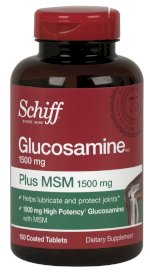

Dành Cho Người Bị Đau Khớp Tạo Chất Nhờn- Thực Phẩm Bổ Sung Arthon Flex, Hoạt Chất Glucosamine Hcl